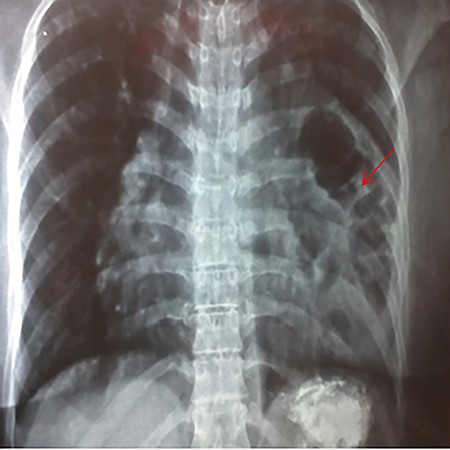

A 35-year-old primigravida female patient complained of mild chest and epigastric pain. Twenty months earlier, she underwent a successful emergent caesarian surgery for preeclampsia, which was performed without complication. Since then, the patient complained of an episodic spasmo-colic pain in the left chest and abdomen that radiated to the left scapula and the upper back. On current presentation, she reported dyspnea and palpitation with sub-sternal heaviness. These symptoms were accompanied by a dry cough, orthopnea and palpitations. No change in bowel movements or any other complaints were reported or evident. She reported no history of surgery except for the cesarean section, which was uncomplicated. She reported no previous trauma, her family history was insignificant and the physical examination was normal. Pfannenstiel incision scar was well-healed with no erythema or drainage, and no tenderness or palpable masses were present around the scar or underneath it. Chest X-ray (Fig. 1) showed an enlarged cardiac silhouette, a closed left costo-diaphragmatic angle and an opacity that covered the left lower border of the heart and the left diaphragmatic dome. The right hemi-thorax was normal. Pleural effusion was suspected and thoracentesis was conducted. The drained fluid labs showed a neutrophilic exudative bloody liquid. Following this, a barium swallow (Fig. 2) was performed, which showed abdominal viscera to be herniated into the thoracic cavity with no other abnormalities. Chest and abdomen computed tomography (CT) scan with contrast (Fig. 3) showed a non-homogeneous opacity in the left side of the thoracic cavity that pushed the heart and other mediastinal components to the right. It was compatible with herniated abdominal viscera, suspected to be either a Morgagni hernia or as a result of a neglected trauma to the diaphragm (although the patient denied any trauma). Surgery was indicated using the thoracic approach. Under general anesthesia, the left chest was entered through the sixth intercostal space, and the thoracic cavity was found to be normal with no signs of hernia. The pericardium was opened and explored; the great omentum and colon were found to be protruded through the diaphragm into the pericardial sac. A defect of 5 cm in diameter was found in the central tendon of the diaphragm (Fig. 4). The adhesions between the pericardium, myocardium and the viscera were released. The viscera were then reduced back into the abdominal cavity through the hernia. The hernia was primarily sewed with running proline suture then covered with 5 × 5 cm proline patch which was supported with a pericardium patch. Finally, the pericardium was partially closed. Three days later, the chest drain tube was removed and the patient discharged in good status. A 2-week follow-up chest X-ray showed no abnormalities and monthly chest X-rays were indicated for a year, and were all normal.

Showing an abnormal barium swallow with viscera (red arrow) in the left hemi-thorax.